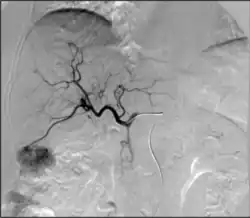

Angiography: Sometimes referred to as traditional angiography, catheter angiography or digital subtraction angiography (DSA). A small needle is inserted into a blood vessel, then exchanged for a catheter over a wire. The catheter is directed at the vessel to be studied, and contrast is directly injected to evaluate the lumen under video X-ray. This is an older technique than modern CT angiography or MR angiography, but provides unique advantages. With a catheter in place, provocative maneuvers can be performed such as breath holds or instillation of vasodilators, to evaluate a patient's blood flow dynamically. This can reproduce symptoms and identify functional abnormalities in a vessel that a static CT or MR imaging cannot.[80][81] Angiography provides the basis for all endovascular therapy.

Takayasu arteritis angiography